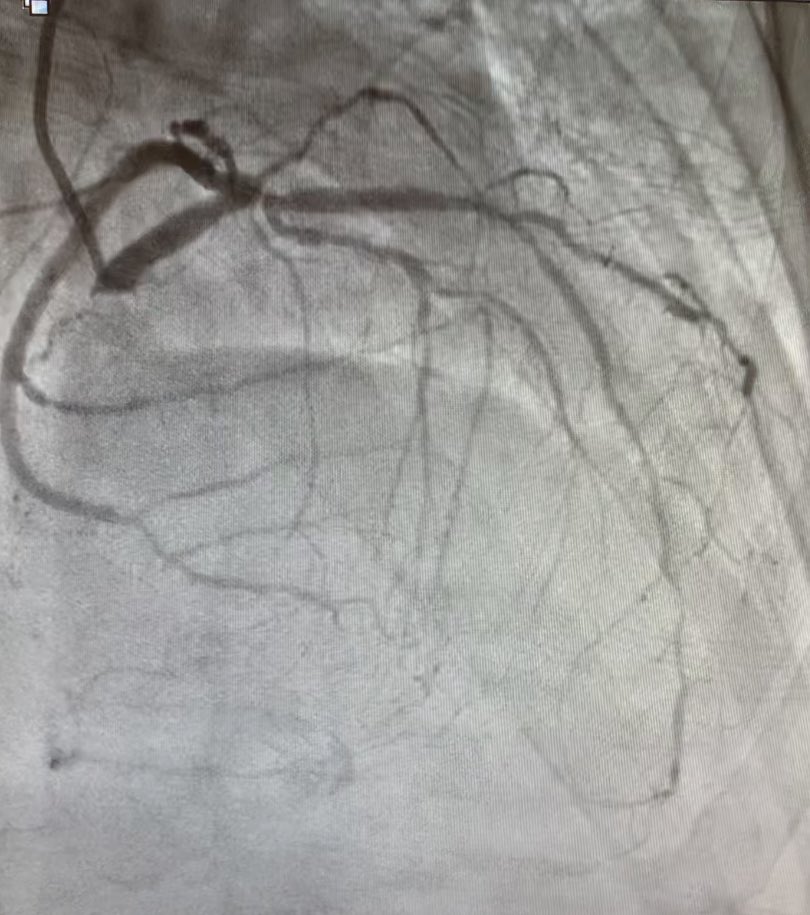

#safefemoral #protectedpci 62 m anterior stemi ivus guided into left main . Ef 50% at d/c

istentem's tweet image. #safefemoral #protectedpci 62 m anterior stemi ivus guided into left main . Ef 50% at d/c